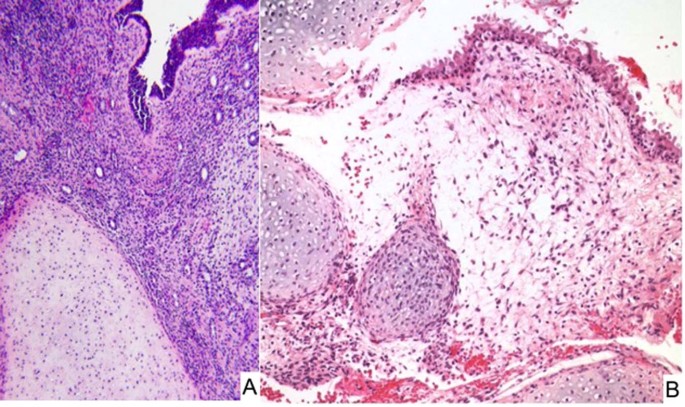

Pleuropulmonary blastoma-like peritoneal sarcoma

Primitive sarcoma resembling PPB presenting in the peritoneal cavity has been reported in 7 children from 3 to 14 years with the fallopian tube (4 cases), pelvic sidewall (2 cases) and serosa of the colon as the apparent primary site117. None of these children had a past or contemporaneous history of PPB or other DICER1–associated neoplasms. The tumors all shared the morphologic spectrum of PPB including cystic spaces with underlying primitive small cells with or without rhabdomyoblastic differentiation (sarcoma botryoides-like pattern and nodules of cartilage similar to type I PPB; multilocular peritoneal cysts without underlying primitive mesenchymal cells resembling type IR PPB; and the remaining cases with cystic and solid features or a purely solid multipatterned primitive sarcoma of type II/III PPB (Fig. 14A, B). These similarities to PPB suggested a temporal progression from a simple multiloculated cyst to a solid multipatterned primitive sarcoma; however, this remains to be confirmed with the inclusion of additional cases. McCluggage and associates have reported three cases similar to our experience in addition to an ovarian ERMS119. Not only were there the overlapping morphologic features of PPB as in our series117, but biallelic loss of function RNase IIIb DICER1 mutations were detected in six cases with available DNA and germline DICER1 mutations were also present in four of the five patients119.